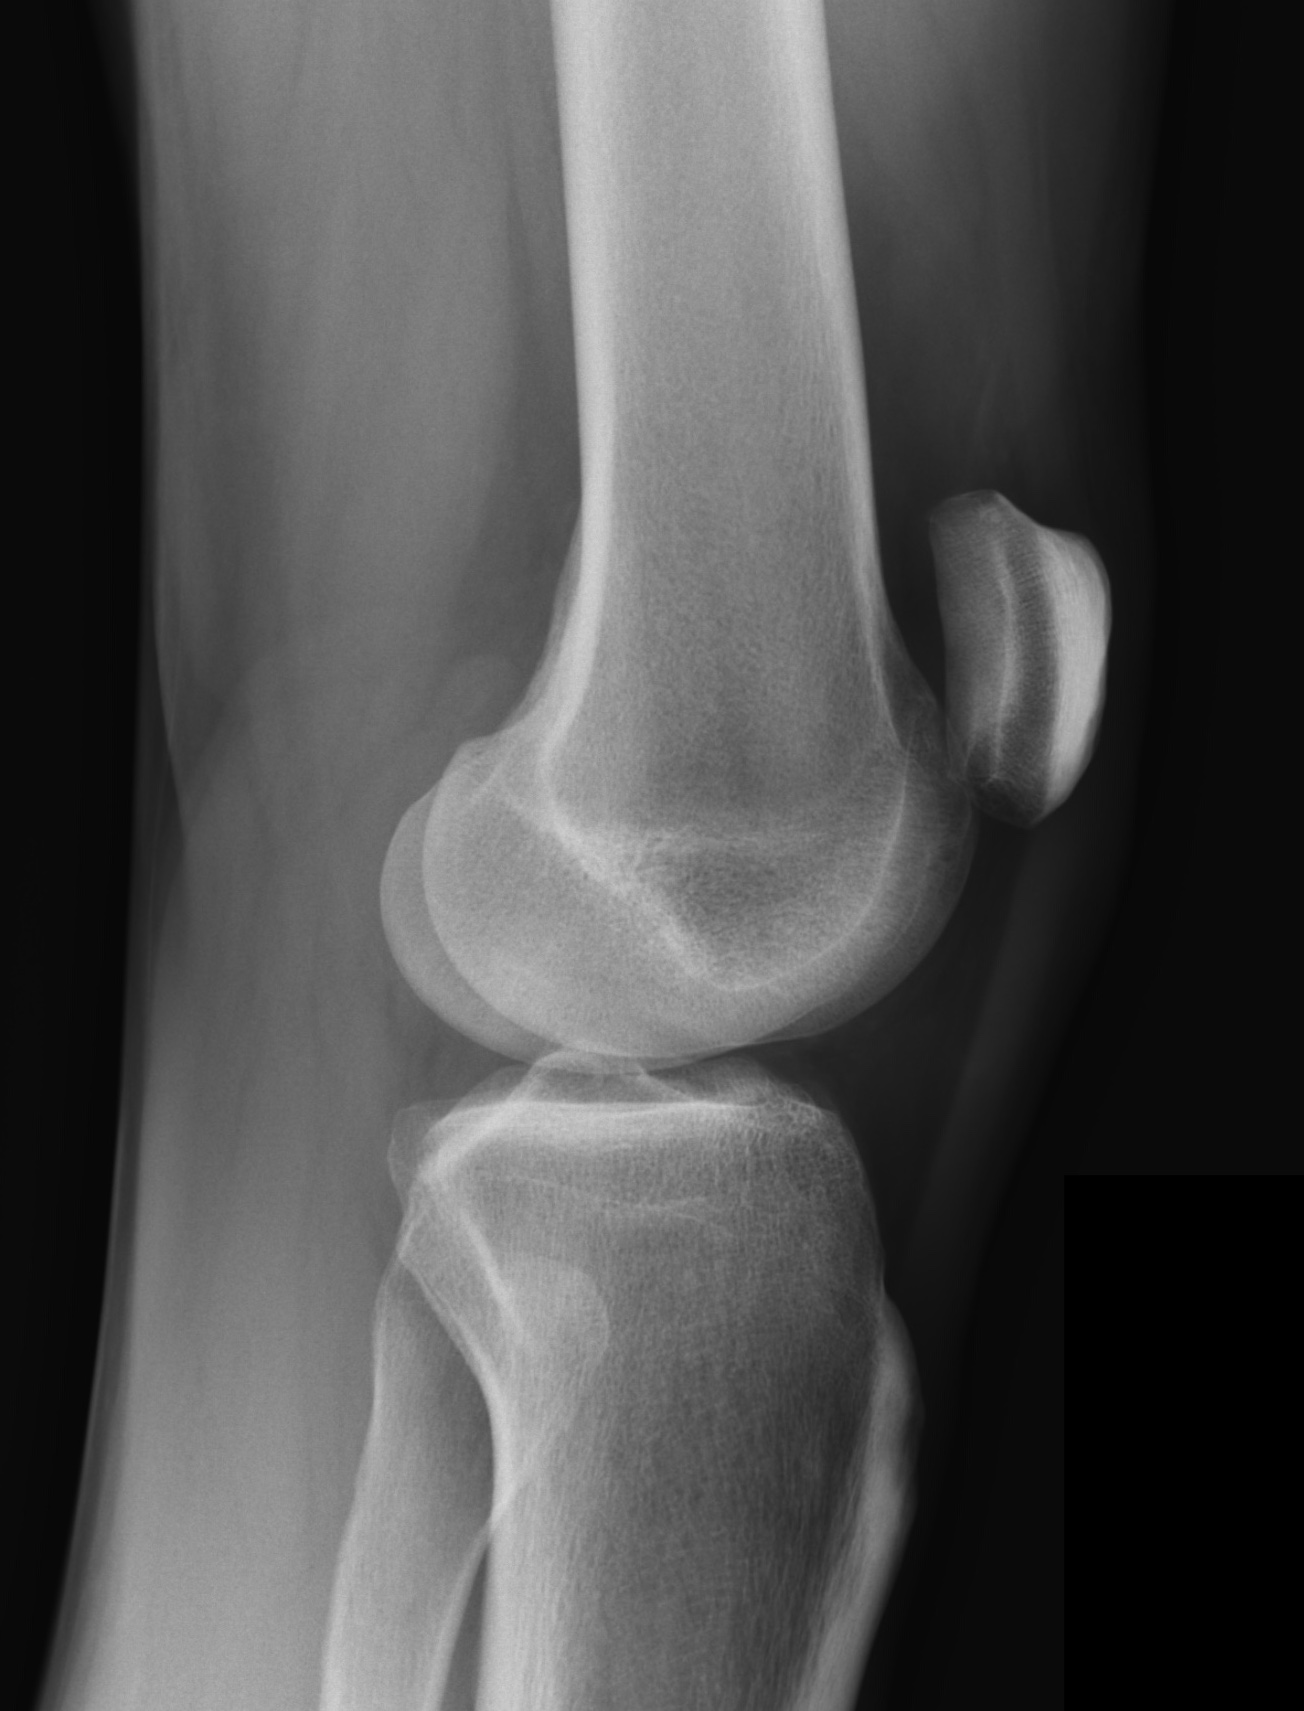

Die Beurteilung zur Knieendoprothese bei Gonarthrose basiert auf der aktuellen S2k-Leitlinie der DGOU. Diese Leitlinie wurde erstmals im April 2021 veröffentlicht und zuletzt am 13.03.2023 umfassend überarbeitet. Sie vereint sowohl evidenzbasierte Erkenntnisse als auch breite Expertenkonsens.